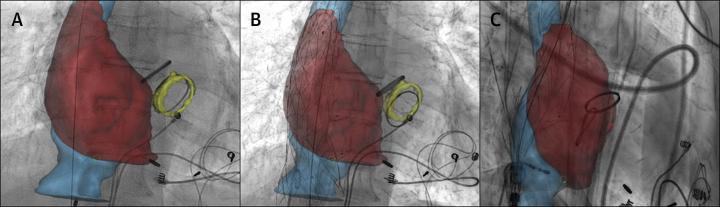

Figure 4.

Intraprocedural Fusion Imaging

Intra-procedural fusion imaging with projection of 3-dimensional reconstructions and landmarks within fluoroscopic live imaging (Video 1); (A) anteroposterior view before implantation; (B) anteroposterior view after implantation; and (C) lateral view after implantation.

The intervention (Video 1) was conducted under general anesthesia with intubation and availability of fluoroscopy. Transfemoral endovascular access was gained and a pigtail catheter was positioned within the RA. After obtainment of 2 contrast agent sequences, registration for intraprocedural projection of 3-dimensional reconstructions and markers was performed (Figure 4, Video 1). An ablation catheter was positioned as an additional landmark at the inferior landing zone according to the projected IVC reconstruction. Meanwhile, crimping and loading of the stent was performed. Following introduction of the sheath (26-F), the deployment apparatus was inserted and its tip positioned beneath the azygos vein confluence. Controlled top-down deployment of the stent was executed, and valve functionality was tested via angiography before the final stent release. Intraprosthetic and intra-atrial angiography confirmed good placement and absence of major endoleaks. Invasive measurements of central venous and RA pressures showed an inversely correlated decrease of mean central venous pressure from 28 mm Hg to 21 mm Hg and increase of mean RA pressure from 18 to 24 mm Hg after implantation (Table 1). A significant increase in the V wave of the right atrial curve was observed during hemodynamic evaluation after implantation (Figure 5). Endovascular closure of the right femoral vein was performed using 2 ProGlide vascular closure systems (Abbott).